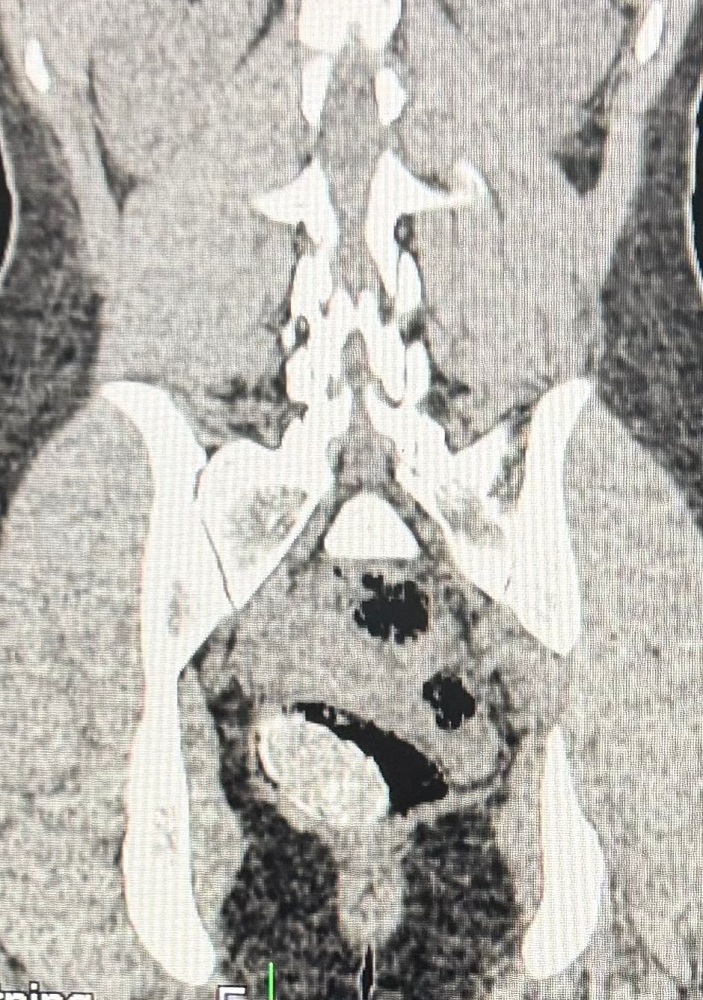

Diante da fundada suspeita, a visitante foi encaminhada ao Hospital Regional de Irecê para realização de exame de imagem complementar (tomografia computadorizada), que confirmou a presença de corpo estranho em cavidade corporal.

Após orientação médica, a própria envolvida realizou, de forma voluntária, a retirada do material, sendo constatado aproximadamente 0,60 gramas de substância análoga à cocaína, acondicionada em invólucro específico para ocultação interna.